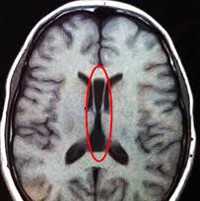

Червь мозжечка — это структура, расположенная между его половинами и несущая в себе проводящие нервные волокна. При аномалии Денди-Уокера он может быть представлен небольшой щелью или широким пространством между гемисферами органа. При неполном отсутствии червя щелевидное расширение образуется лишь в нижней его части. На фоне патологии этого отдела наблюдается недостаточное развитие и мозжечковых полушарий.

Именно дефект мозжечкового червя в виде расщелины считается характерным признаком аномалии Денди-Уокера, позволяющим отличать ее от недоразвития на фоне других пороков мозга.

Более, чем в половине случаев синдрома Денди-Уокера у детей помимо описанных структурных аномалий обнаруживаются и другие дефекты мозга — недоразвитие или отсутствие мозолистого тела, мозговые кисты, недоразвитие или отсутствие извилин, смещения серого вещества относительно его правильной локализации, что еще больше усугубляет течение и без того тяжелой патологии.

- Гипоплазия мозжечковых гемисфер, наличие широкой щели между ними;